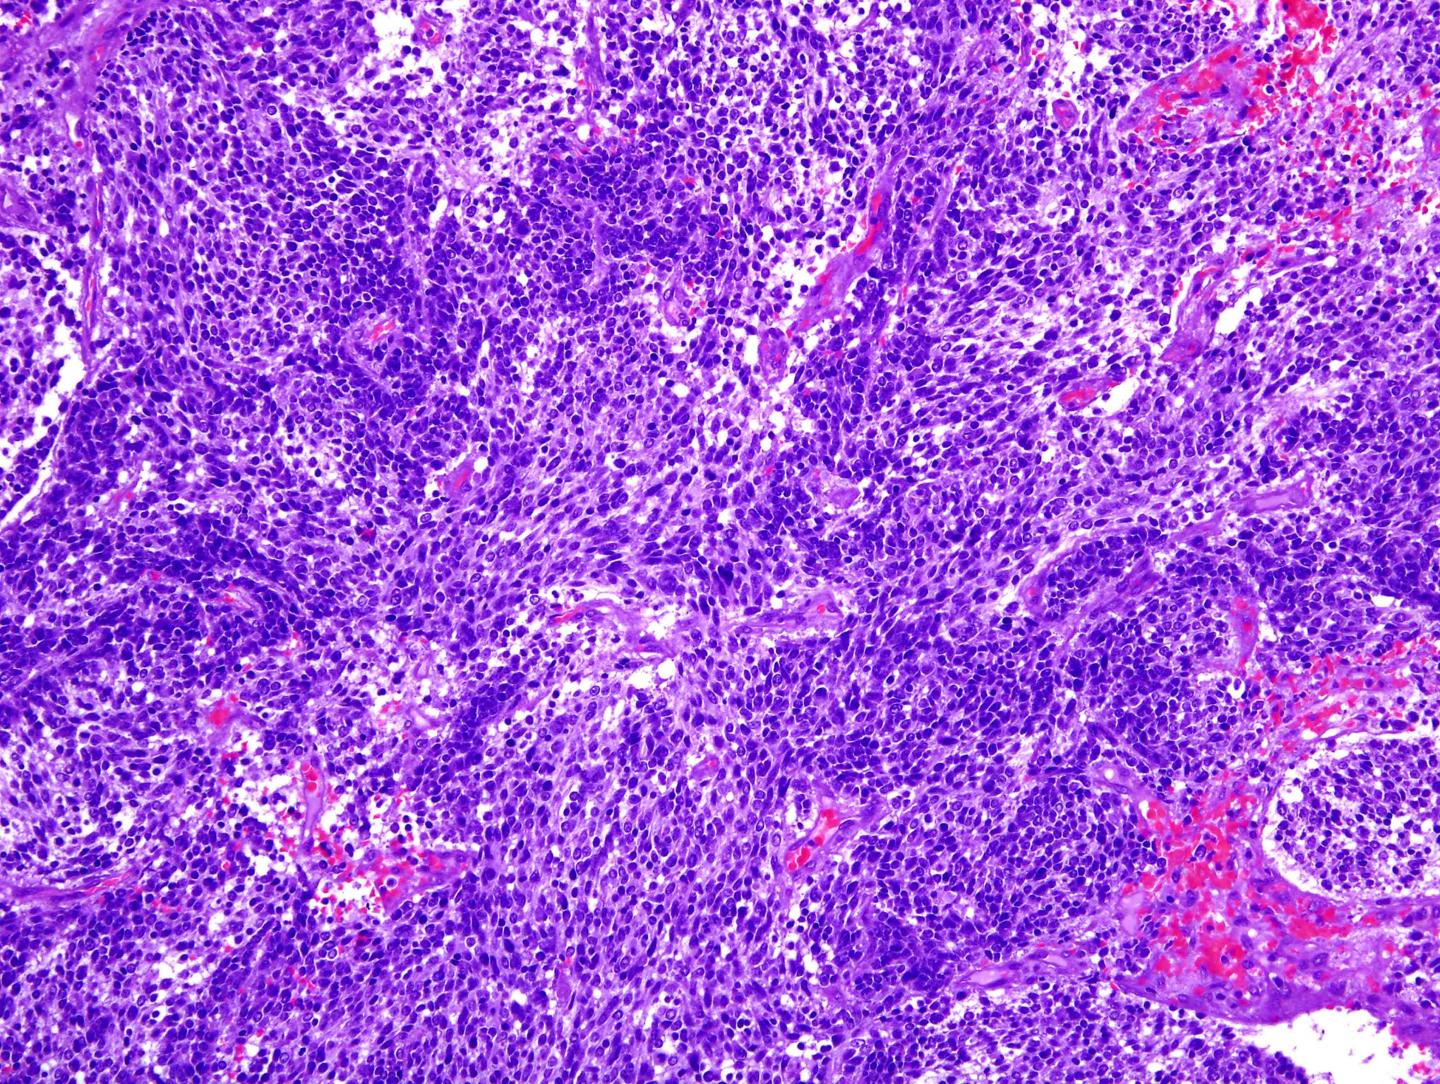

Image of a Glioblastoma, the M [IMAGE] EurekAlert! Science News Releases